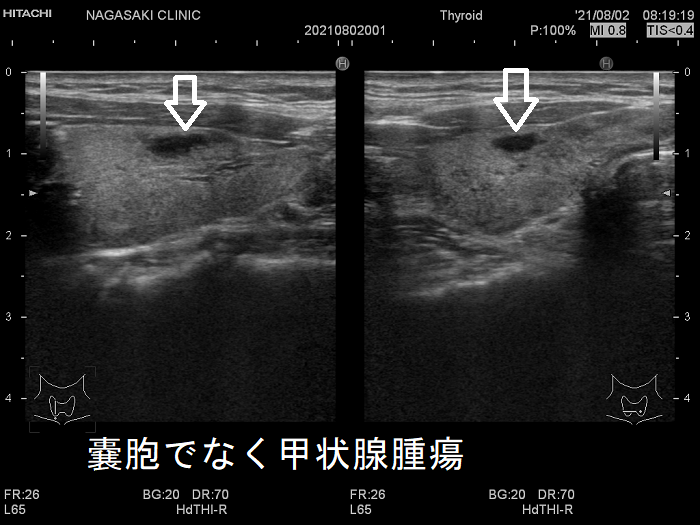

8. 石灰化した甲状腺腫瘍・橋本病甲状腺内の石灰化  甲状腺嚢胞と間違えられる甲状腺腫瘍

甲状腺のう胞に見えるが実は甲状腺腫瘍

甲状腺のう胞(甲状腺嚢胞)に見えるが甲状腺腫瘍 超音波(エコー)画像;低エコー(真っ黒)で、内部にコロイド様物質があるように見えるため、甲状腺のう胞(甲状腺嚢胞)と間違えます。

甲状腺のう胞に見えるが実は甲状腺腫瘍 eFlow

甲状腺のう胞(甲状腺嚢胞)でなく甲状腺腫瘍  eFlow(イー フロー);内部血流が、はっきり見えて甲状腺腫瘍なのがわかります。

たとえば、通常Bモードでは、

1. のう胞(嚢胞)に見えても、高感度パワードプラーで低流速の細い血管が検出され、実は真っ黒な(極めて低エコーな)甲状腺腫瘍 [甲状腺のう胞(甲状腺嚢胞)に見えるが甲状腺腫瘍]

2. 充実性腫瘍に見えても、高感度パワードプラーで低流速の細い血管が検出されず、実はただの甲状腺のう胞腺腫(甲状腺嚢胞腺腫)(内部の不均質な実質様エコーは粘稠なコロイド物質)

だったなど、臨床診断が覆る場合があります。特に1.の場合は、甲状腺腫瘍甲状腺のう胞(甲状腺嚢胞)と間違えると大変な事になります。極めて低エコーな甲状腺腫瘍は、甲状腺乳頭癌甲状腺濾胞癌甲状腺髄様癌甲状腺悪性リンパ腫の可能性があるからです。